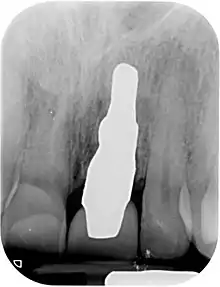

Root analogue dental implant

A root-analog dental implant (RAI) – also known as a truly anatomic dental implant, or an anatomical/custom implant – is a medical device to replace one or more roots of a single tooth immediately after extraction. In contrast to common titanium screw type implants, these implants are custom-made to exactly match the extraction socket of the specific patient. Thus there is usually no need for surgery.

RAIs are custom made to perfectly fit the tooth socket of a specific patient immediately after tooth extraction. Therefore every implant is unique. As an optimized root-form it is much more than a simple 1:1 replica of a tooth. Since it exactly fills the gap left after the tooth is extracted, surgery is rarely needed. The implant can be produced from a copy of the extracted tooth, an impression of the tooth socket, or from a CT scan or CBCT scan.[3] The advantage of a CBCT scan is that the implant can be produced before extraction. With the former methods, it takes one or two days to fabricate an implant.

A root analogue implant can be fabricated from zirconium dioxide (zirconia) or titanium. Successful titanium RAIs have been three-dimensionally printed as porous one-piece implants, using CAD software.[4] However, zirconia is the preferred material, because it is more esthetic in color, with no grey discoloration visible through gums.[5][1]